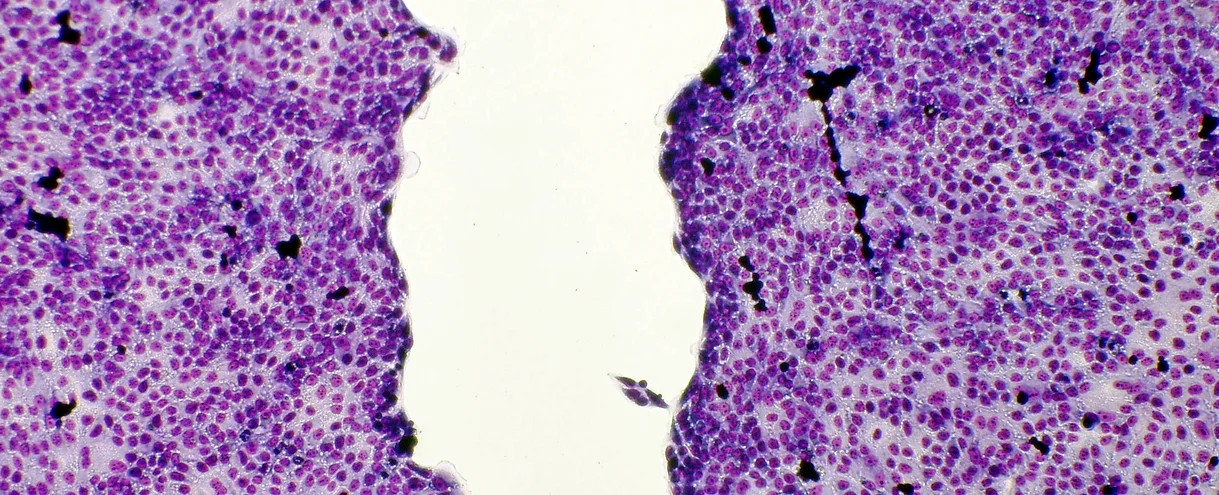

Example of cell regeneration

Compared to the untreated control group (image above) the identically created connective tissue cells in the image below increased in size by more than 55% grows together faster resp, regenerated. A ZenPad was placed under these connective tissue cells.